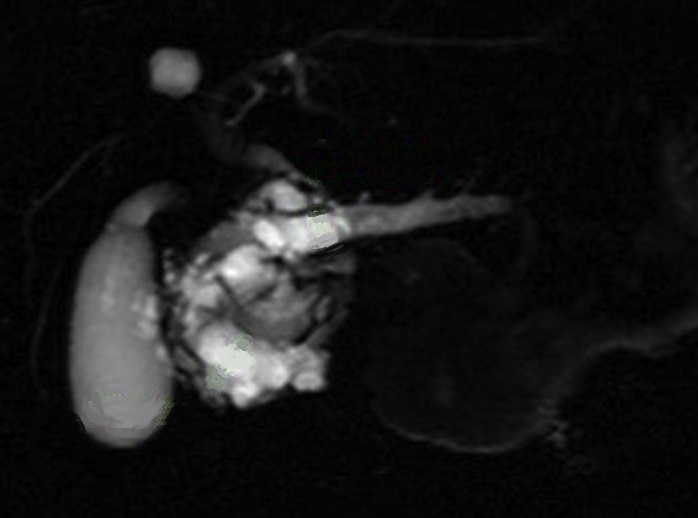

Image radiologique Wirsungo-cholangio IRM

d'une TIPMPde type canaux secondaire du corp pancreas avec image de kyste

multiple , polylobulaire ( fleche rouge ) en

communication avec la CPP . Image radiologique du

canal choledoque et des voies biliaire

intrahepatique sont en vue tres nette . |